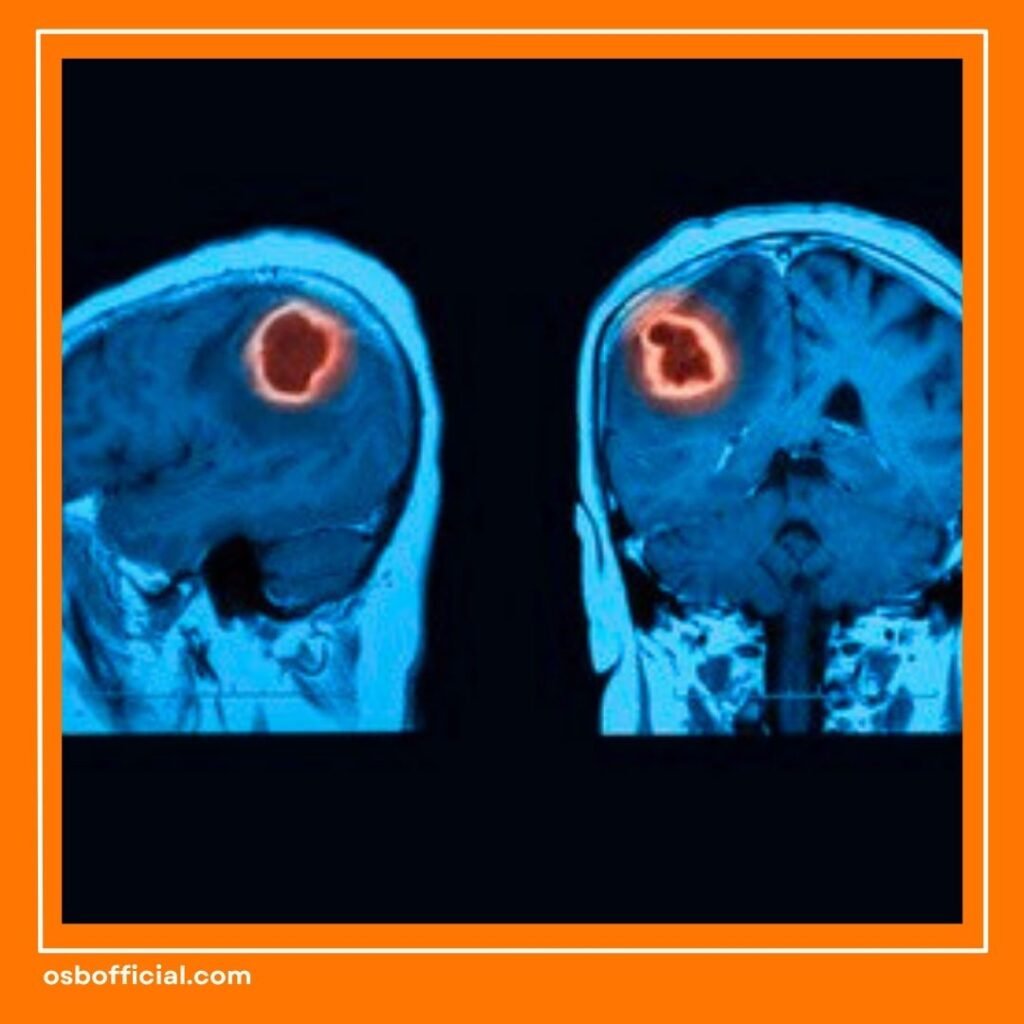

Baca Juga: Waspadai! Ini Tanda Awal Kanker Otak yang Sering Diabaikan